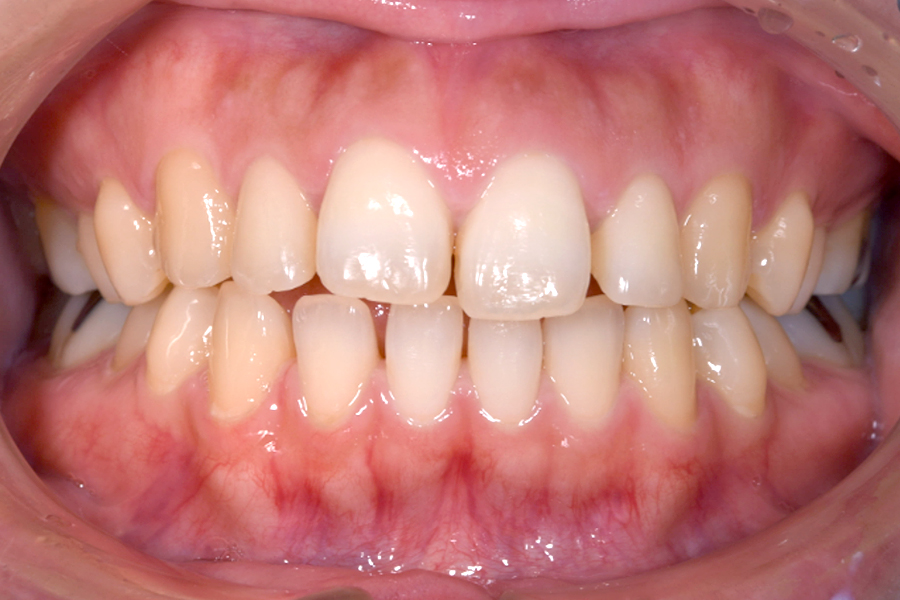

| 主訴 | 見た目を治したい、歯を白くしたい |

|---|---|

| 治療期間 | 1年6か月 |

| 治療費 | マウスピース矯正と ホームホワイトニングセット 1,022,350円(税込) |

| 治療内容 | 目立ちにくいマウスピース矯正 (非抜歯矯正) 歯と歯の間に隙間をつくることにより、歯列弓を広げながら治療を行いました。 また矯正用マウスピースをトレー代わりにし、ジェルを入れてホームホワイトニングを同時に行っております。 |

| 治療のリスク | ・後戻りする可能性があるのでリテーナーを最低でも矯正期間以上はつける必要があります。 ・ホワイトニング後、一時的に痛みが出る場合があります。 |